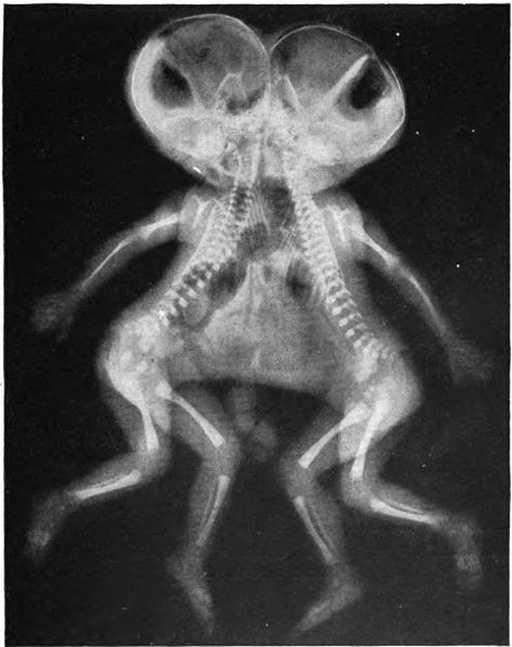

17. 连体双胞胎的X光片。

一些奇怪的X光照片,看完整个人都不好了……-17.jpg